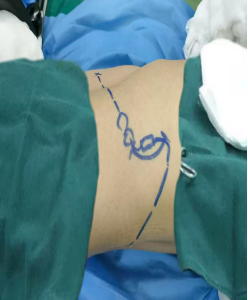

手术过程:体位:右侧卧位,屈膝;切口设计:背部取L3-4椎间隙切口(约2cm),腹部取左髂前上棘弧形切口(约4cm);操作要点:专用穿刺针进入蛛网膜下腔,确认脑脊液通畅后,建立皮下隧道,将分流管自腰部引至腹腔。